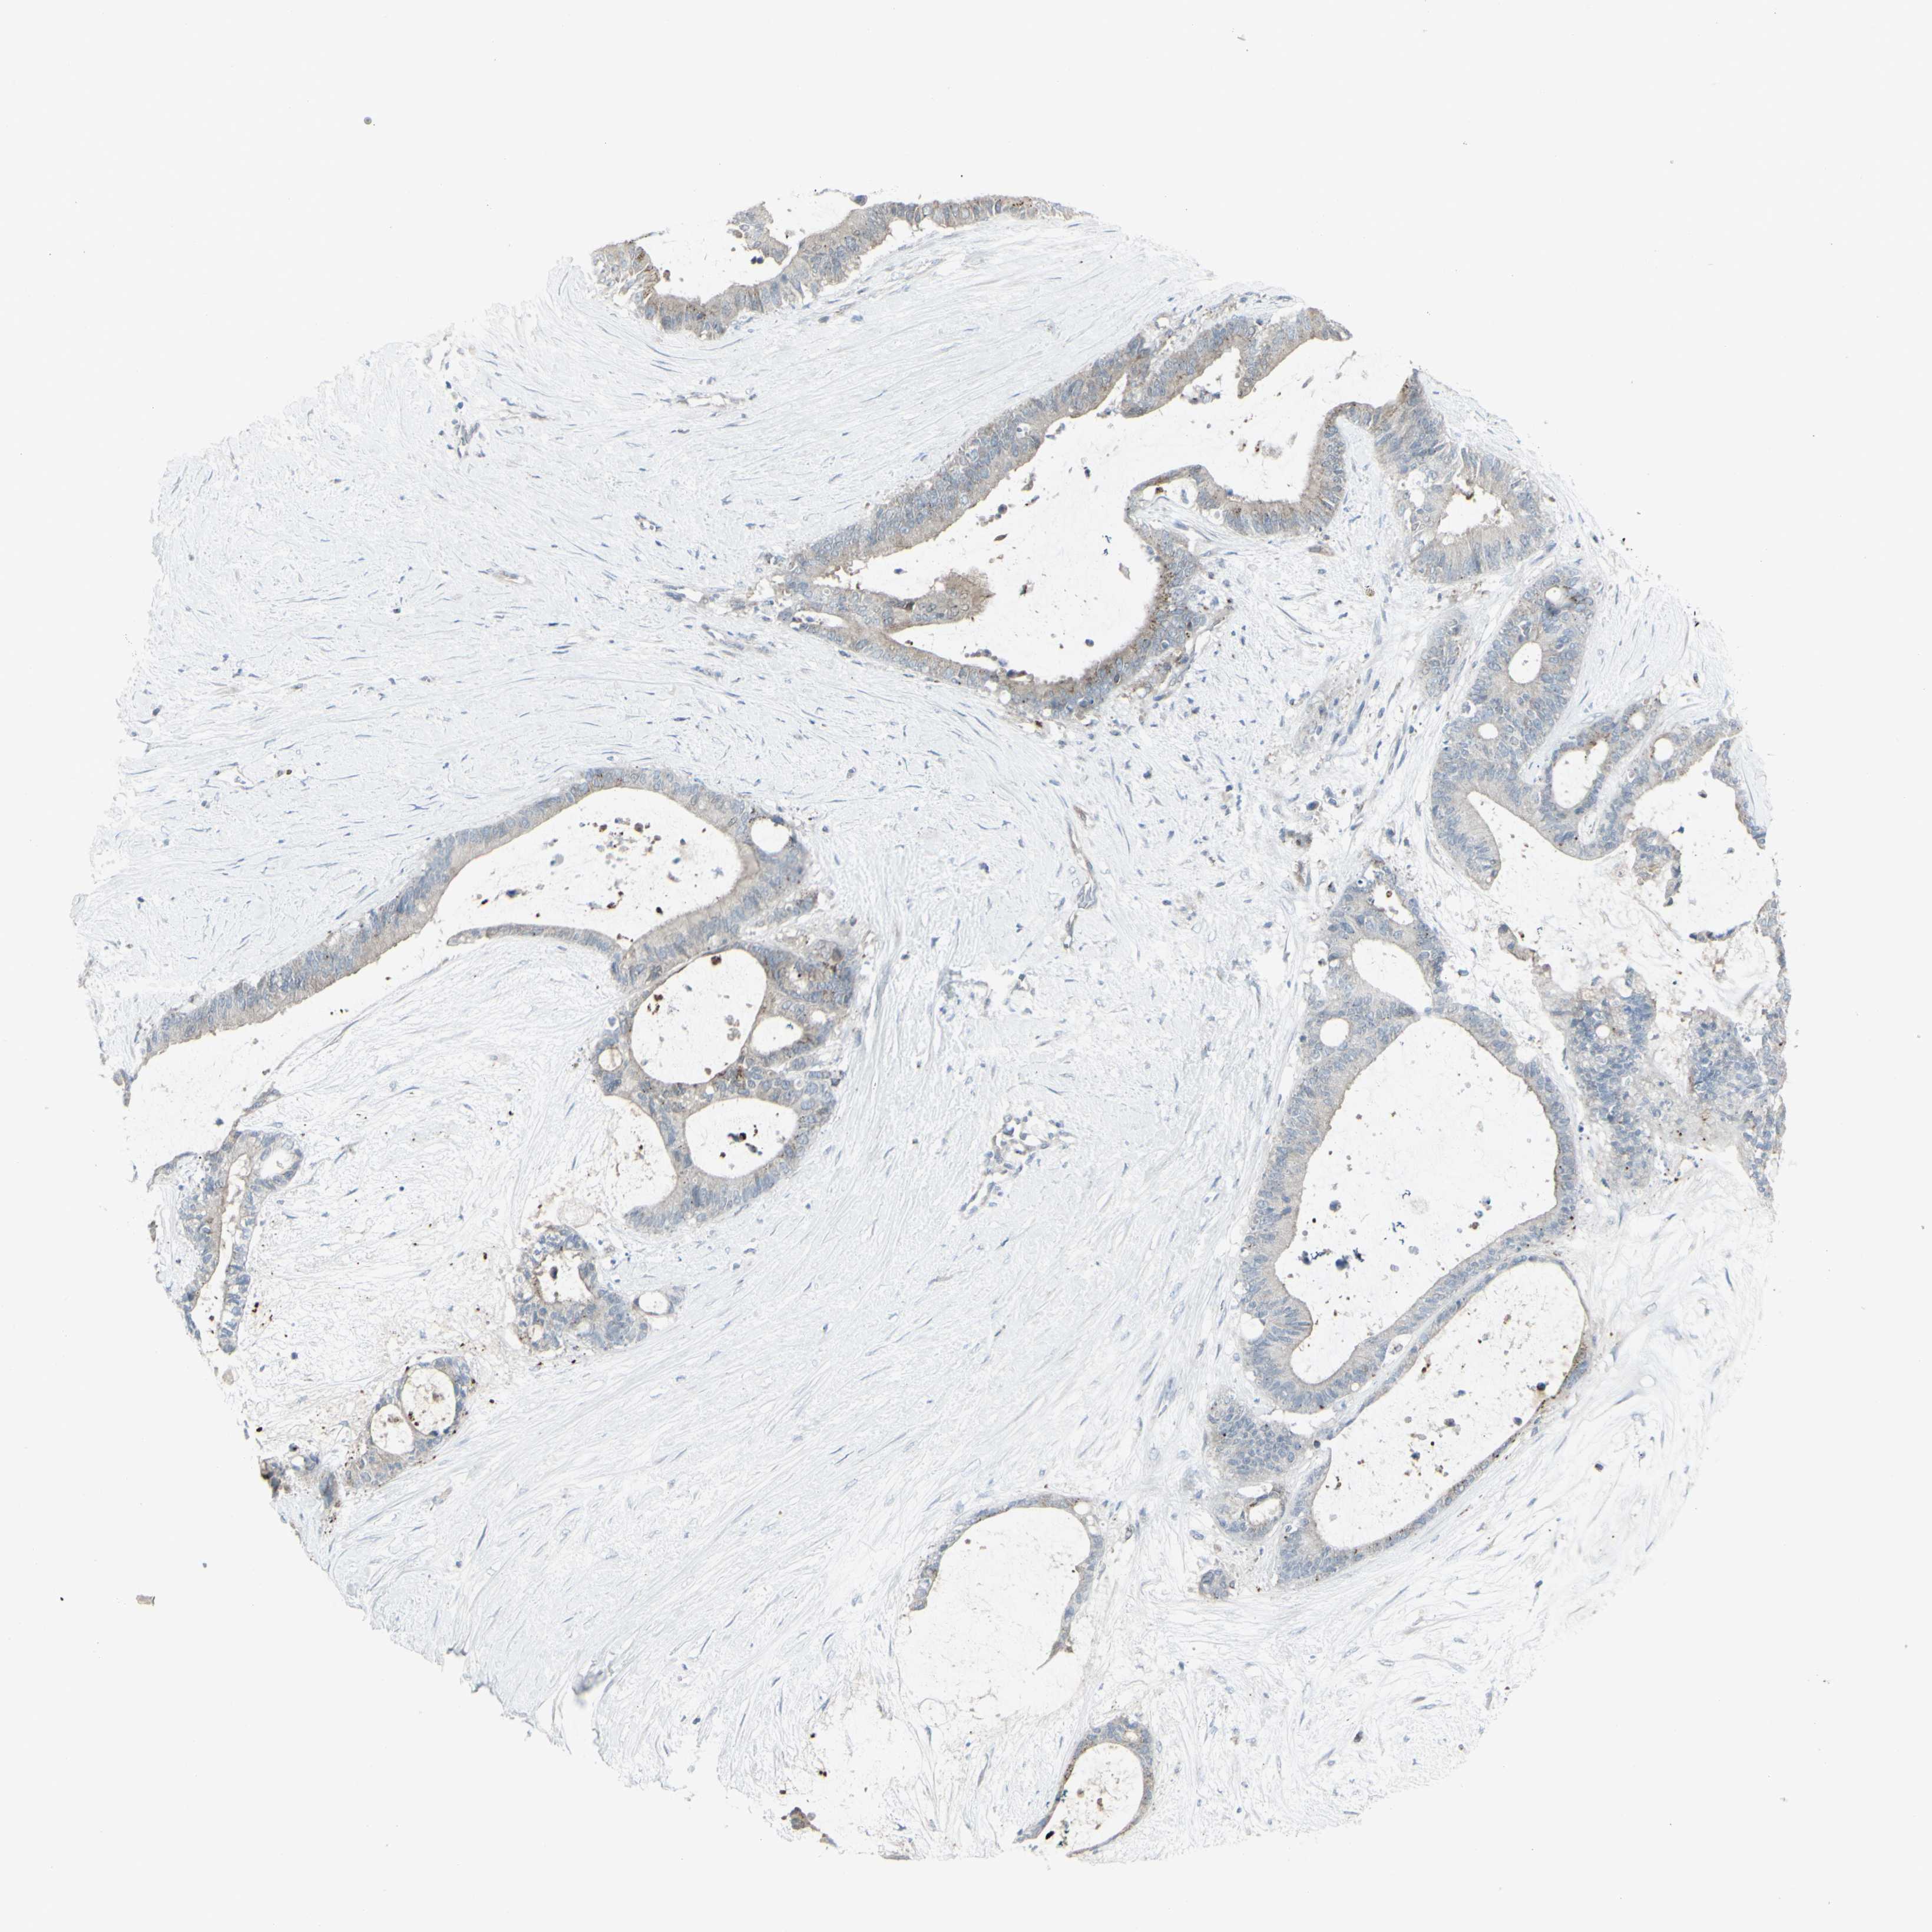

LIVER CANCER - Protein expressioni

A mouse-over function shows sample information and annotation data. Click on an image to view it in a full screen mode. Samples can be filtered based on level of antibody staining by selecting one or several of the following categories: high, medium, low and not detected. The assay and annotation is described here.

Note that samples used for immunohistochemistry by the Human Protein Atlas do not correspond to samples in the TCGA dataset.

Antibody stainingi

Antibody staining in the annotated cell types in the current human tissue is reported as not detected, low, medium, or high, based on conventional immunohistochemistry profiling in selected tissues. This score is based on the combination of the staining intensity and fraction of stained cells.

Each image is clickable and will lead to virtual microscopy that enables deeper exploration of all samples and also displays staining intensity scores, fraction scores and subcellular localization as well as patient and tissue information for each sample.

Antibody HPA011762

Antibody HPA017086

Staining

High

Medium

Low

Not detected

Intensity

Strong

Moderate

Weak

Negative

Quantity

>75%

75%-25%

<25%

None

Location

Nuclear

Cytoplasmic/membranous

Cytoplasmic/membranous,nuclear

Cholangiocarcinoma

Carcinoma, Hepatocellular, NOS